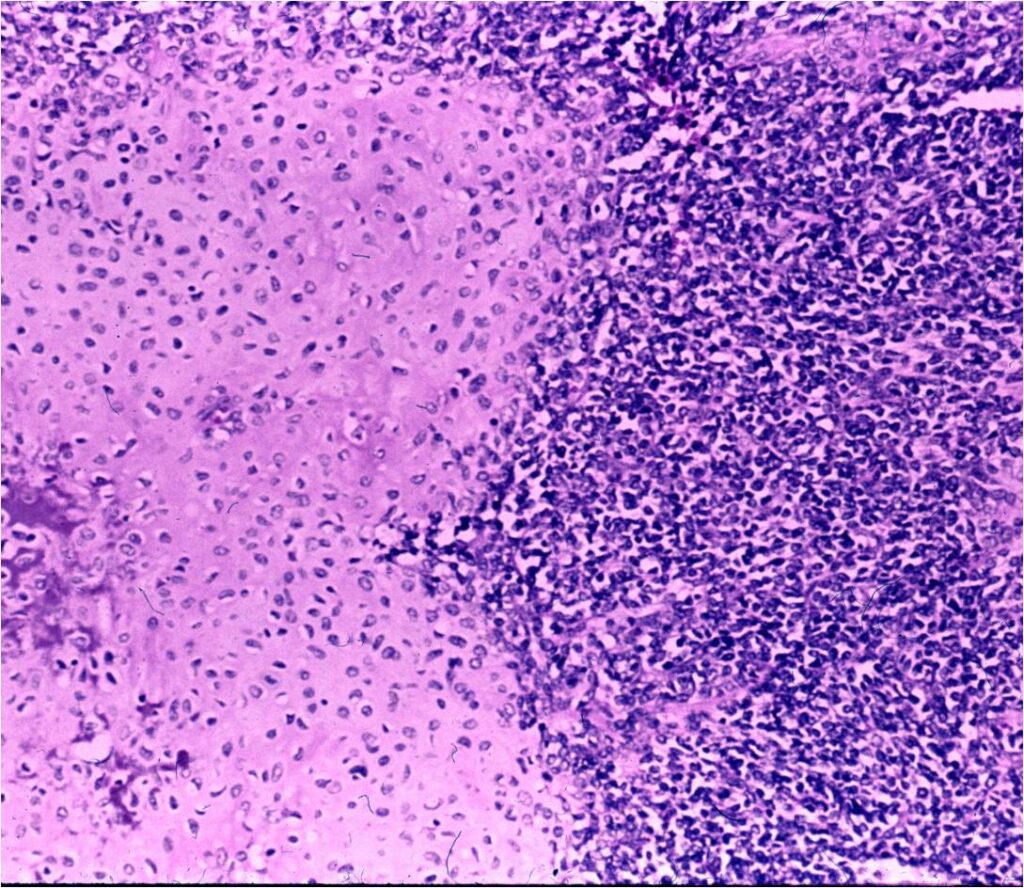

- Neoplastic cells may be small, round, oval, or spindle shaped

- Undifferentiated mesenchymal cells similar to Ewing sarcoma

- Low grade islands of cartilage scattered throughout the mesenchymal cells

- Usually only a small part of lesion

- Cytologically low grade

- Usually sharply demarcated from surrounding stroma

- May contain islands of collagen resembling osteoid

- Lesions are vascular and often have large, anastomosing vessels that impart hemangiopericytoma-like pattern